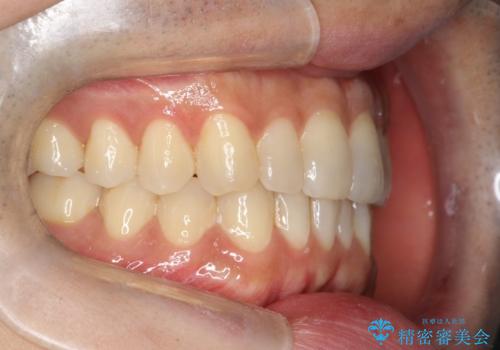

- 前歯の歯並びの改善を希望され来院された患者様です。

初診時の歯並びの状態としては、下顎に中等度のがたつき(叢生)がある状態でした。

抜歯は行わず下顎の奥のスペースを利用して歯をスライドする方法の他に親知らずの抜歯そして上下ともに歯列弓の拡大やディスキング(歯と歯の間の隙間を作る処置)を行い叢生を改善しました。

歯の大きさの不揃いが原因の正中のズレは、ディスキング量を調整することで合わせました。

矯正装置としてはマウスピースを使用しています。